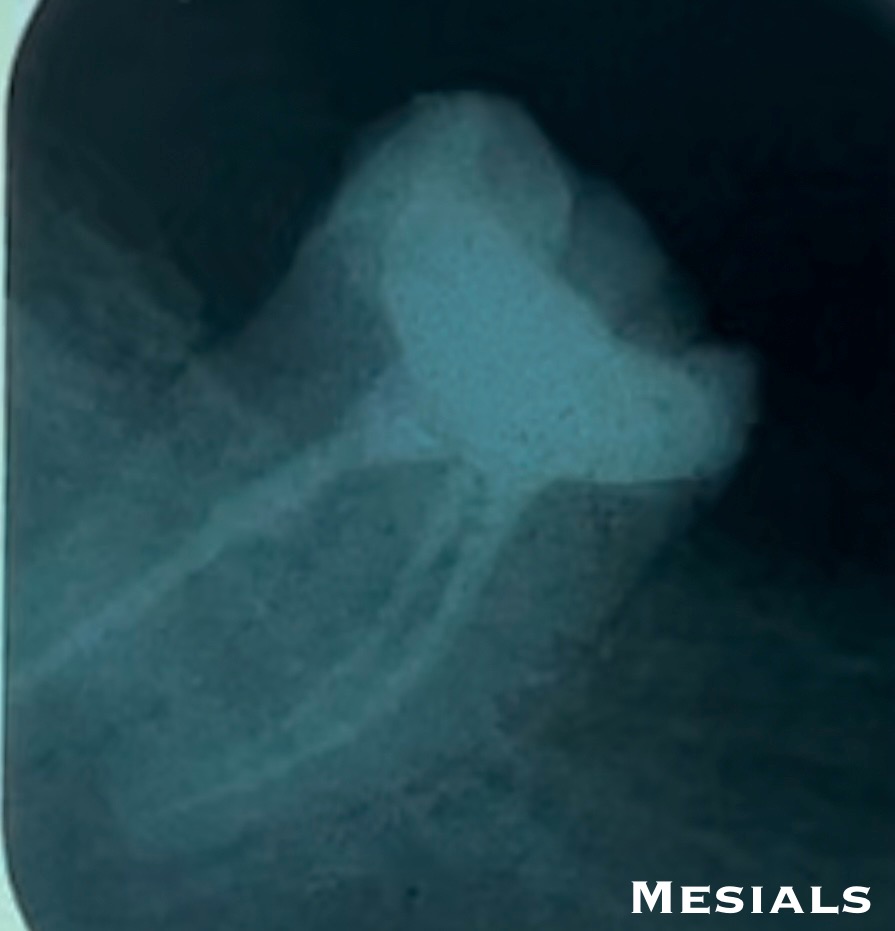

Final x-ray:

- Composite crown.

- Obturation tech. : Single cone with a bioceramic sealer.

X-rays.